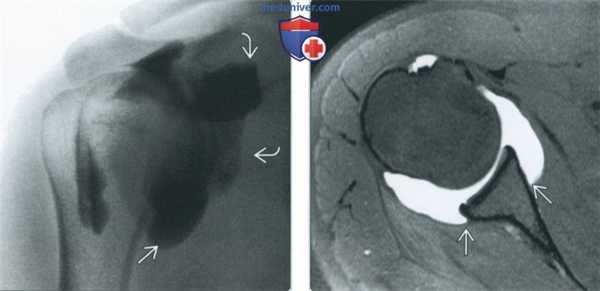

(Слева) Артрография, передне-задняя проекция, пациент с клиническими проявлениями многоплоскостной нестабильности плечевого сустава: визуализируются необычно крупные подмышечный и медиальный завороты.

(Справа) МР-артрография в режиме Т1ВИ FS, аксиальный срез, этот же пациент: определяются крупные передний и задний завороты. С медиальной стороны визуализируются места прикрепления суставной капсулы к лопатке.